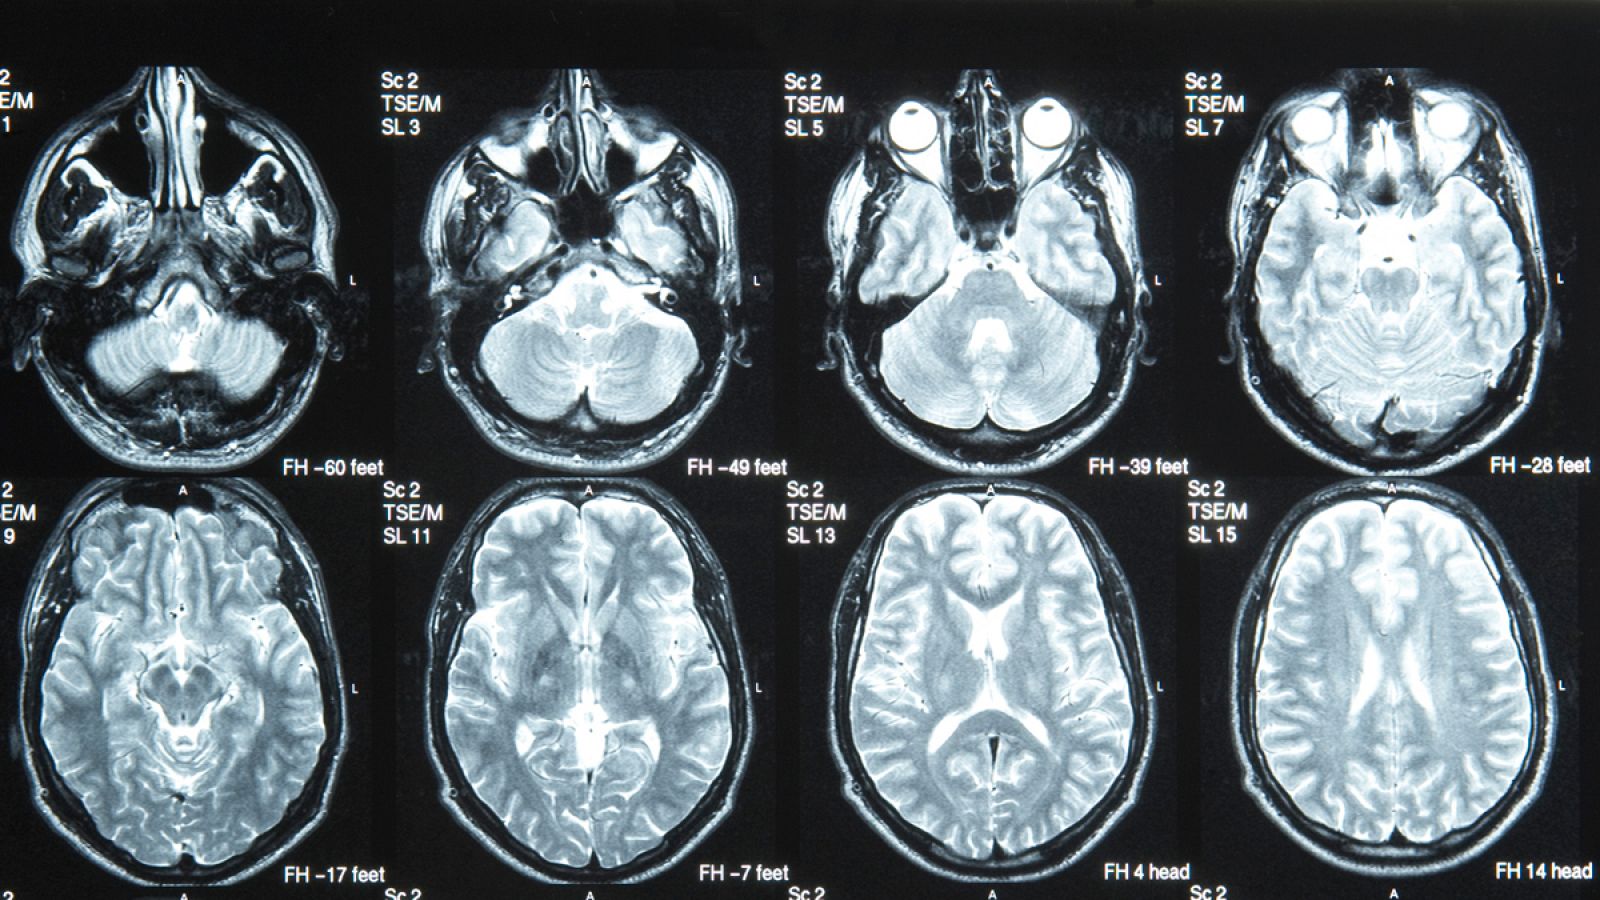

Con seis millones de muertes al año, el ictus o infarto cerebral es la segunda causa de defunción del mundo y la primera de discapacidad en adultos, una prevalencia elevadísima que aumentará con el envejecimiento de la población, y para la que ahora, un equipo de científicas españolas ha sentado las bases de una futura terapia.